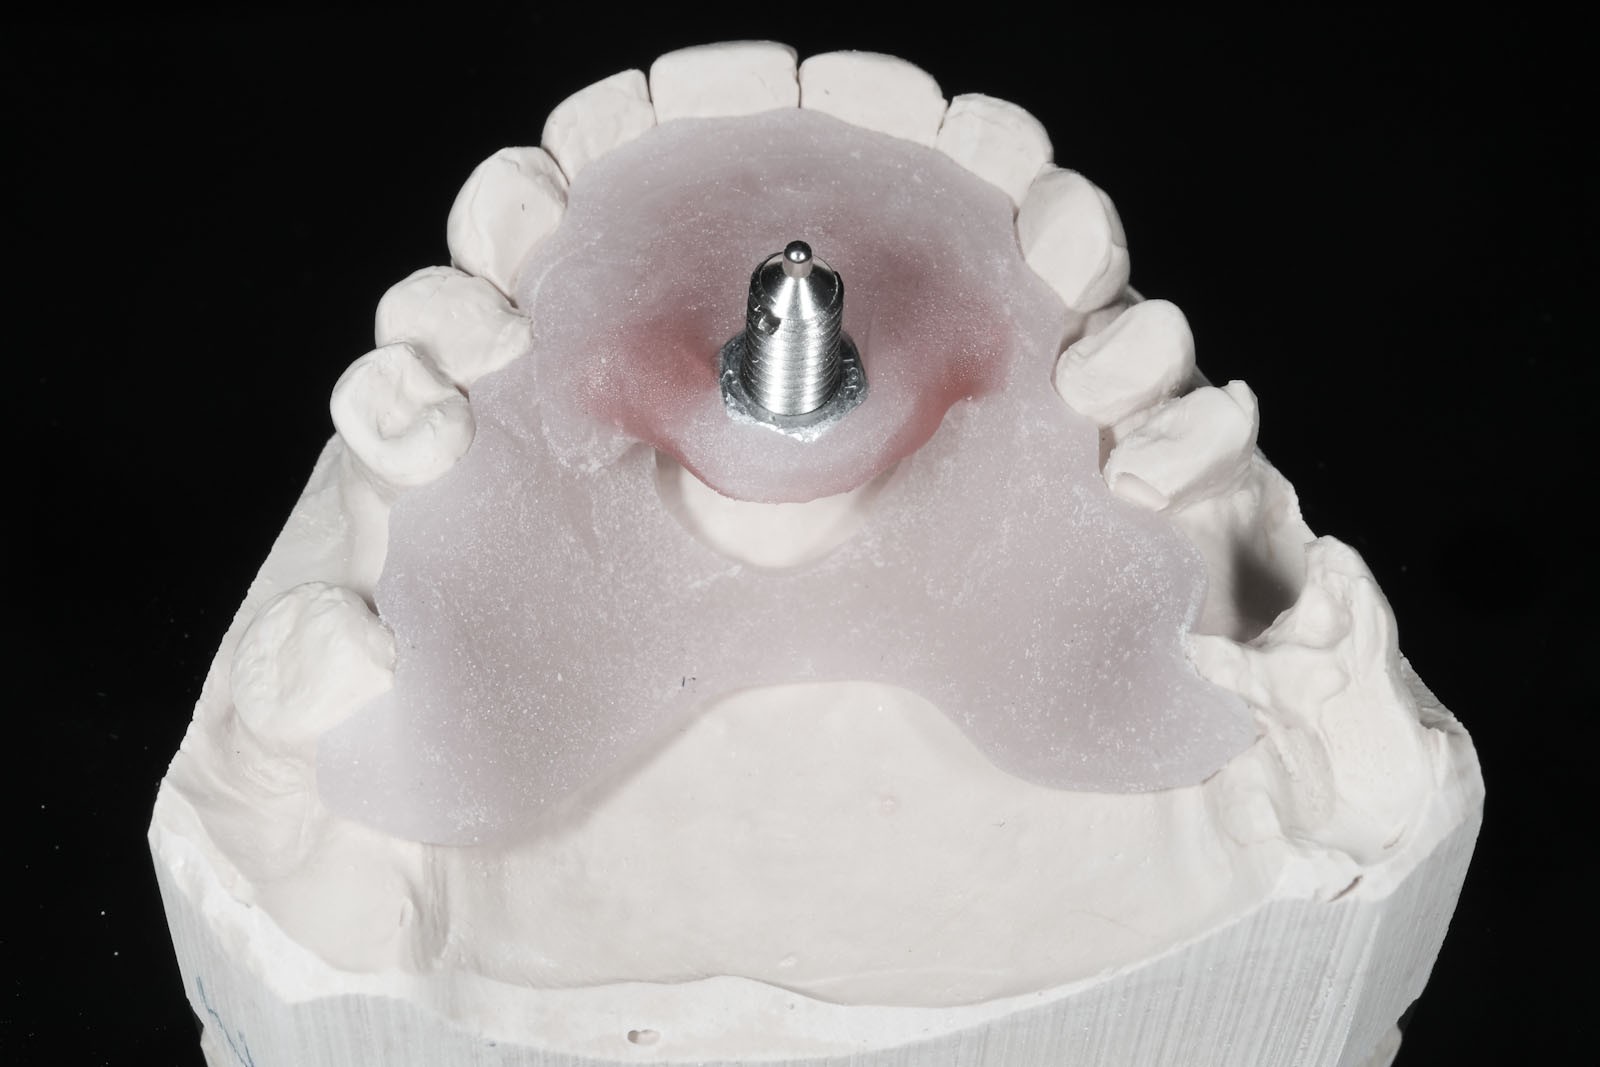

W celu ustalenia wzajemnej relacji żuchwy i szczęki Gerber poleca rejestrację z użyciem centralnego sztyftu podpierającego, który zapewnia równomierne obciążenie podłoża protetycznego i stawów skroniowo-żuchwowych, a także ułatwia centralne ułożenie głów stawowych dzięki trójpunktowemu podparciu żuchwy w stosunku do czaszki.

W pierwszym etapie wykonuje się modele robocze, które są montowane w opracowanym przez prof. Gerbera artykulatorze. Tak zwany condylator pozwala na symulację trójwymiarowych ruchów głów żuchwy. Pozwala na zweryfikowanie poprawności relacji pomiędzy łukiem zębowym górnym a dolnym. Po dokładnym zbadaniu funkcji i morfologii stawu sż, wykonaniu pomiarów oraz ocenie stanu zdrowia zębów zostaje opracowany indywidualny plan leczenia zgodny z uwarunkowaniami pacjenta.

Dzięki zastosowaniu łuku twarzowego możliwy jest pomiar kątów nachylenia torów przesuwania głów żuchwy. Pozwala to na zamontowanie modeli gipsowych w stosunku do stawów skroniowo-żuchwowych i płaszczyzny Campera (linii uszno-nosowej) orientacyjnej w widoku z profilu. Ma to na celu odtworzenie prawidłowej okluzji, czyli odpowiedniej pozycji stykania się zębów górnych z dolnymi.